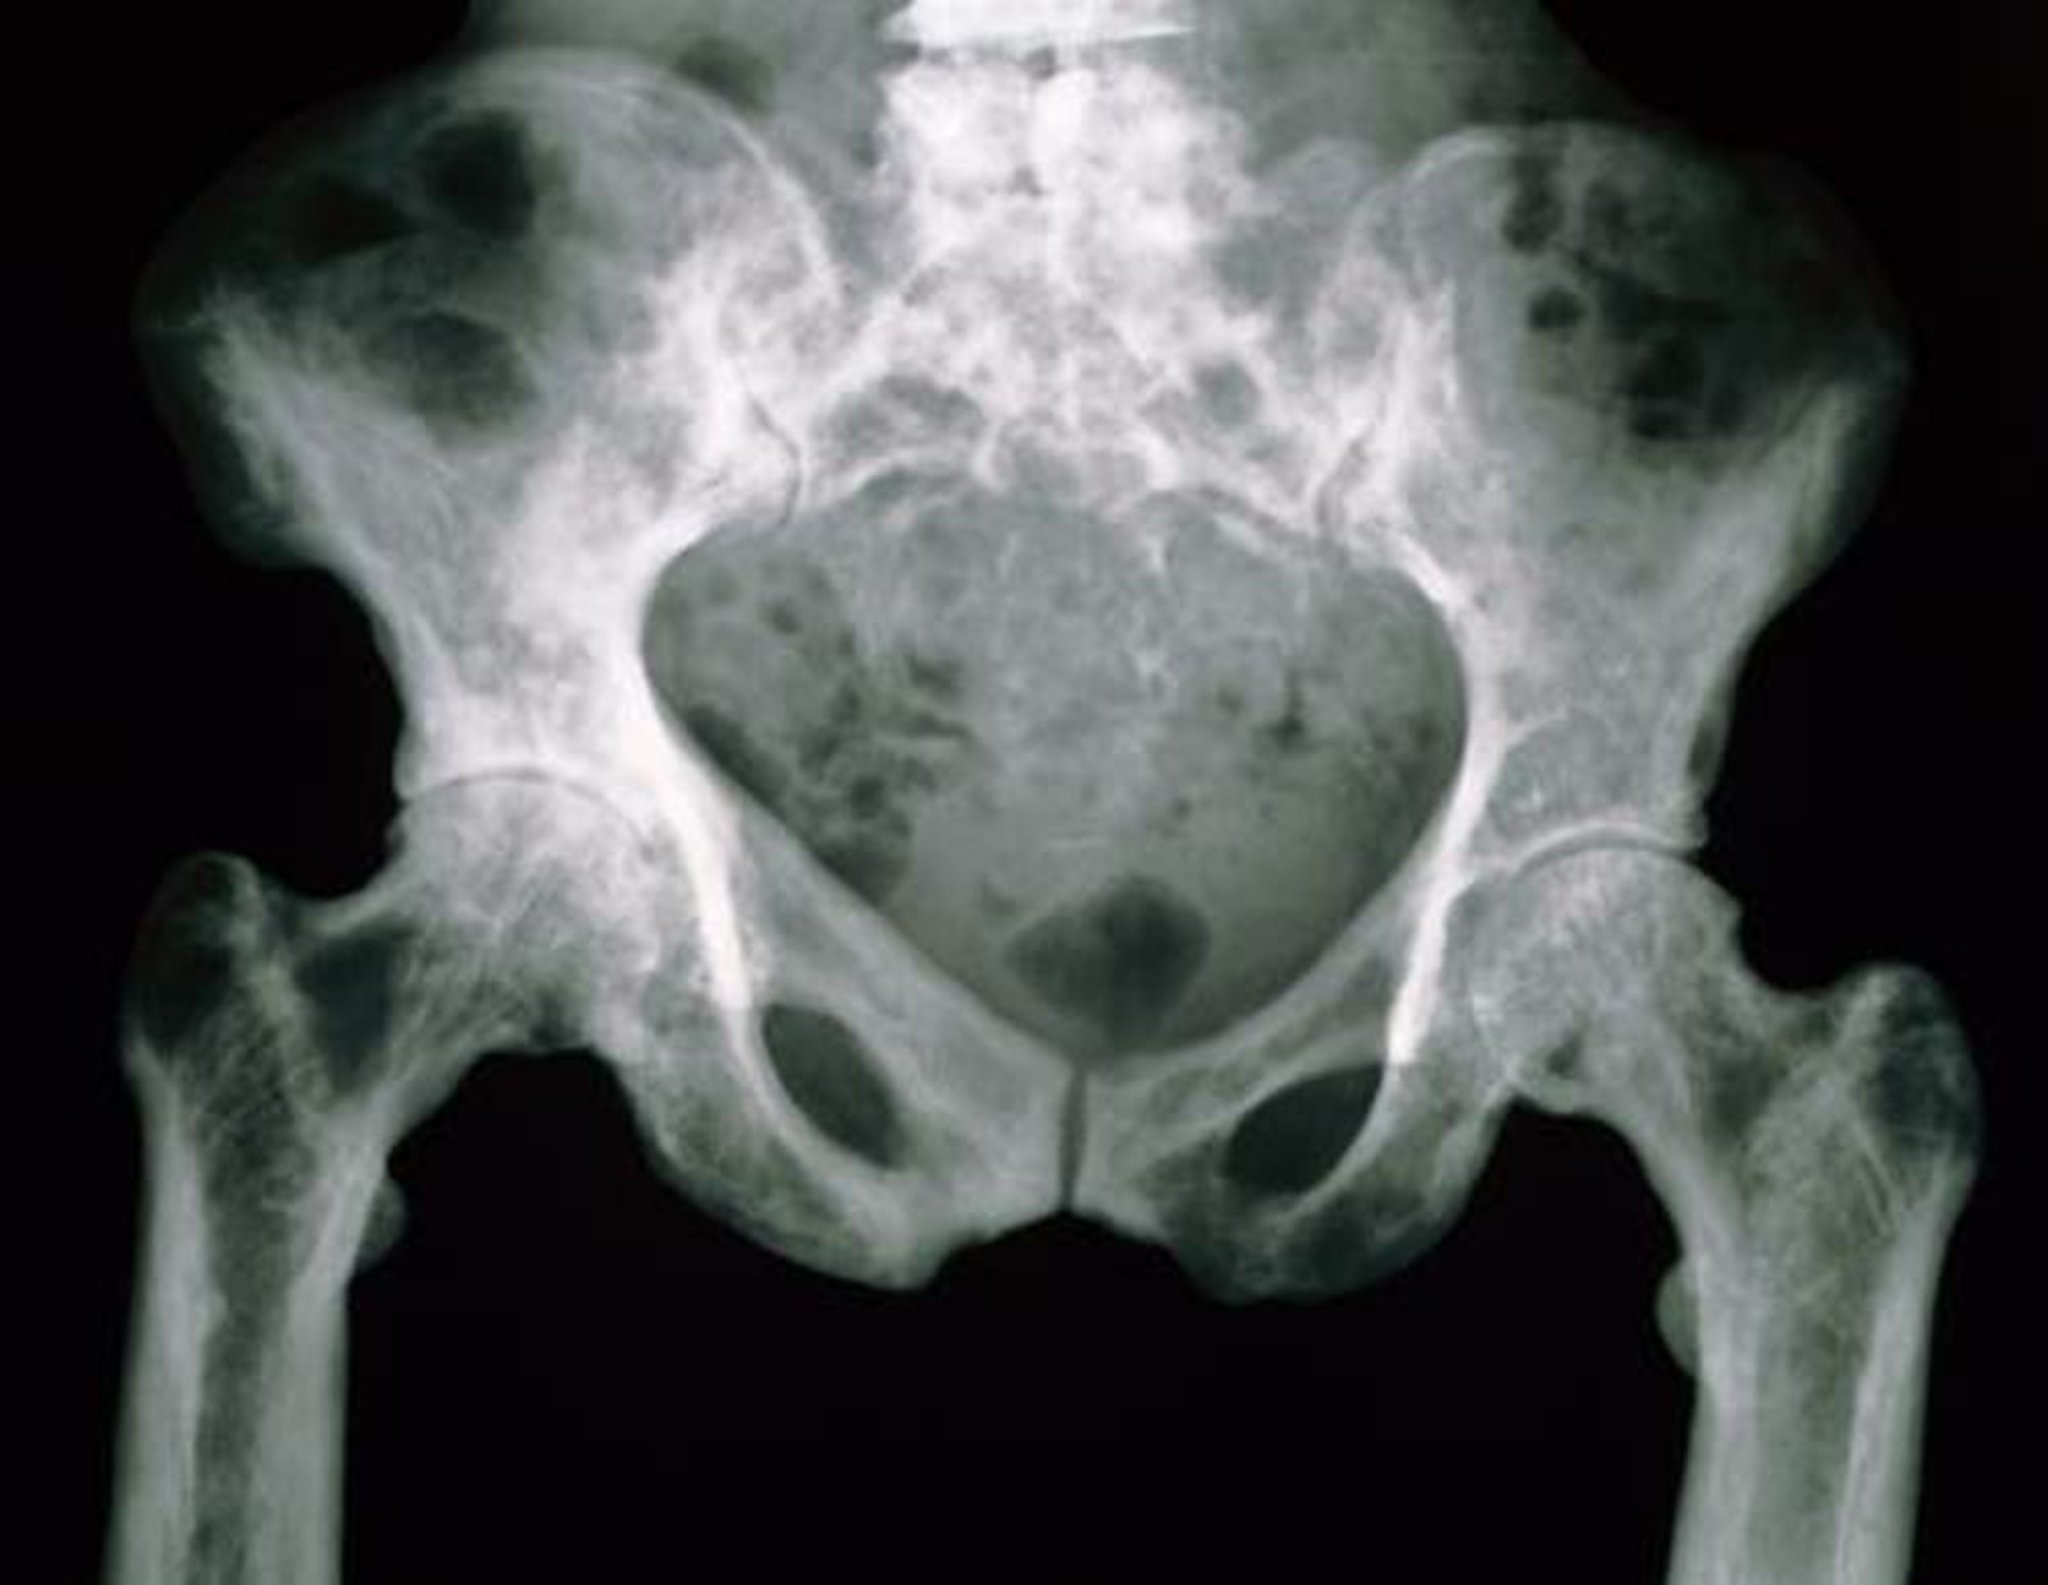

Radiografía de la pelvis en la enfermedad de Paget

En esta radiografía, los huesos pélvicos tienen un aspecto moteado debido a su mayor porosidad.